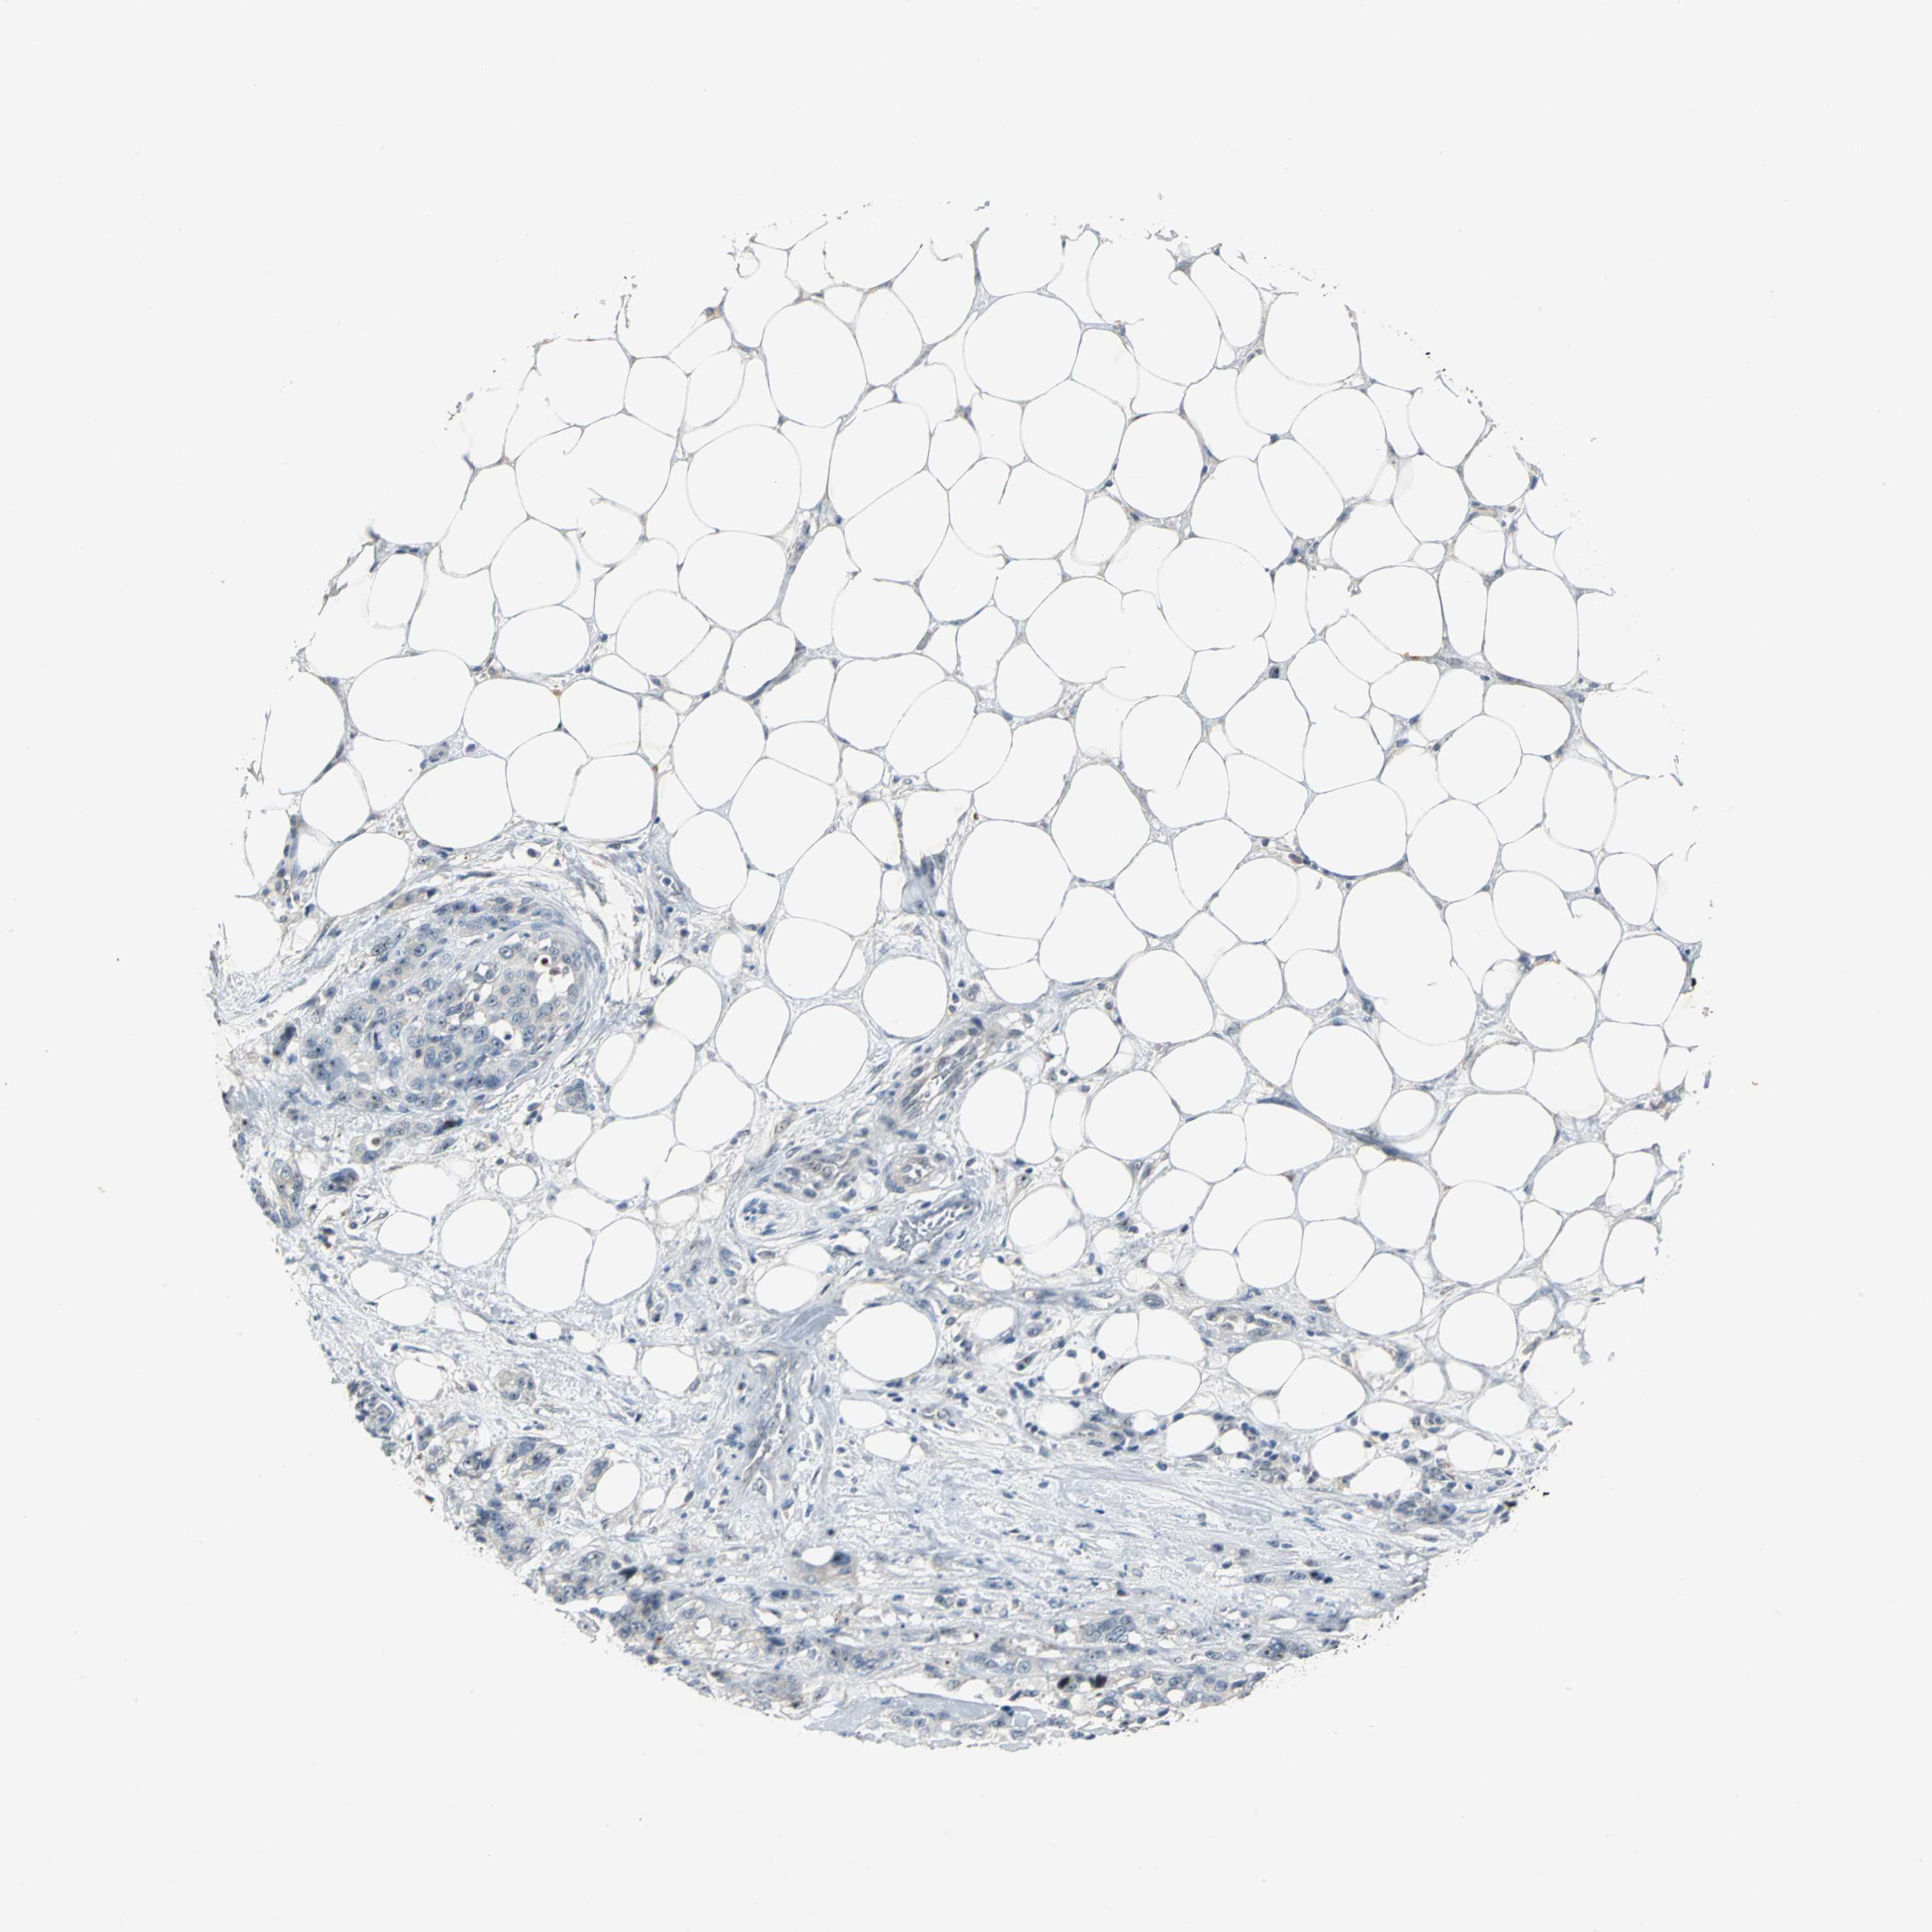

PANCREATIC CANCER - Protein expressioni

A mouse-over function shows sample information and annotation data. Click on an image to view it in a full screen mode. Samples can be filtered based on level of antibody staining by selecting one or several of the following categories: high, medium, low and not detected. The assay and annotation is described here.

Note that samples used for immunohistochemistry by the Human Protein Atlas do not correspond to samples in the TCGA dataset.

Antibody stainingi

Antibody staining in the annotated cell types in the current human tissue is reported as not detected, low, medium, or high, based on conventional immunohistochemistry profiling in selected tissues. This score is based on the combination of the staining intensity and fraction of stained cells.

Each image is clickable and will lead to virtual microscopy that enables deeper exploration of all samples and also displays staining intensity scores, fraction scores and subcellular localization as well as patient and tissue information for each sample.

Antibody HPA005466

Staining

High

Medium

Low

Not detected

Intensity

Strong

Moderate

Weak

Negative

Quantity

>75%

75%-25%

<25%

None

Location

Nuclear

Cytoplasmic/membranous

Cytoplasmic/membranous,nuclear

Adenocarcinoma, NOS

Adenocarcinoma, metastatic, NOS